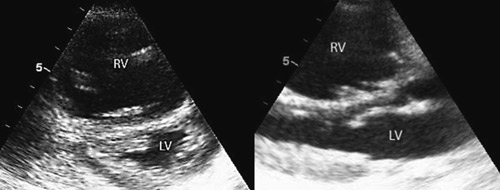

En 20 år gammel kvinne besvimte på stasjonen etter en cirka to timers togreise. I akuttmottaket var hun blek, satt høyt på båren, var uttalt motorisk urolig, dyspneisk og klaget over brystsmerter. Systolisk blodtrykk var 140 mm Hg, puls regelmessig ca. 80 slag/min og pulsoksimetri viste verdier < 85 % (SpO₂). Etter kort tid inntraff det sirkulasjonskollaps med pulsløs elektrisk aktivitet. Det ble startet basal hjerte-lunge-redning og etter 3–4 minutter var det følbar egenpuls i a. carotis, men ikke i a. radialis. Hun våknet til og var svært urolig, men kunne svare bekreftende på p-pillebruk. Pasienten pustet spontant, men ble støttet med 100 % oksygen på maske. SpO2 var <85 %, men det var usikker måling pga. dårlig perifer pulsasjon. Ekkokardiografisk undersøkelse ca. ti minutter etter innkomst viste en hyperkinetisk venstre ventrikkel med svært redusert fylling. Høyre ventrikkel var betydelig dilatert og hypokinetisk. Ventrikkelseptum bukte inn i venstre ventrikkel. Det var ingen tegn til perikardvæske eller hjertetamponade (fig 1). EKG viste sinustakykardi med frekvens 140 slag/min, QRS-bredde 0,12 mm, høyre grenblokk-morfologi med akse + 90°, ST-elevasjon 3 til ca. 10 mm i standardavledninger II, III, aVF samt V2-V4 og ST-depresjon 2 mm i standardavledninger I og aVL (fig 2). Ny sirkulasjonsstans inntraff ca. 15 minutter etter innkomst, og hun ble intubert og hjerte-lunge-redning kontinuert.

Ut fra alder, p-pillebruk, betydelig hypoksi og ekkokardiografiske funn vurderte vi lungeemboli som den mest sannsynlige diagnosen. Lungeemboli gir varierende grad av blodstrømobstruksjon gjennom lungearteriene. Dette kan gi redusert fylling (preload) til venstre ventrikkel, og ekkokardiografisk vil det kunnes påvises en hyperdynamisk og tom venstre ventrikkel (fig 1). Hjerteminuttvolumet vil reduseres og kunne føre til blodtrykksfall og sirkulasjonskollaps.

Ekkokardiografi viste tegn på en hemodynamisk signifikant lungeemboli. Det er vanlig å se de funn vi gjorde: dilatasjon av høyre ventrikkel, redusert høyresidig kontraktilitet, økt diameter av høyre ventrikkel i forhold til venstre ventrikkel og deviasjon av septum mot venstre side. Man kan også se dilaterte proksimale pulmonalarterier, endret blodstrøm i utløpstractus på høyre side, trikuspidalinsuffisiens med jethastigheter omkring 3–3,5 m/s og utvidet v. cava med redusert inspiratorisk kollaps. Pasienter med normal ekkokardiografisk undersøkelse vil ha mindre sannsynlighet for signifikant lungeemboli (4). Et isolert høyre ventrikkel-infarkt vil kunne gi liknende ekkokardiografiske funn, men vanligvis ikke en slik betydelig dilatasjon av høyre ventrikkel med tegn på økte systoliske trykk.